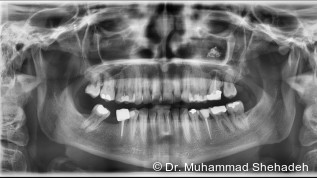

Auf Facebook geistert seit einiger Zeit ein Video umher, das für viel Aufregung unter der Zahnärzteschaft sorgt. Zu sehen ist ein blaues Gel, das direkt auf die Karies aufgetragen wird und nach einer kurzen Einwirkzeit mitsamt der geschädigten Zahnsubstanz einfach ausgeschabt werden kann.

Hinter dem Video steckt die argentinische Firma Brix Medical Science, die so ihr Produkt Brix3000® promotet. Die neue Wunderwaffe gegen Karies verspricht eine schnellere und schmerzfreie Entfernung ohne Bohren. Das Gel basiert auf dem Enzym Papain, einem Bestandteil der Papaya. In mehreren Studien wurde die Wirksamkeit der chemomechanischen Kariesentfernung mit der der herkömmlichen Beseitigung mittels rotierender Instrumente verglichen und deren Wirksamkeit bestätigt.

Der Vorteil des Gels: Es wirkt nur auf die geschädigte Zahnsubstanz, die sich nach einer Einwirkzeit von zwei Minuten ganz leicht ausschaben lässt. Mit dem unbeschädigten Dentin tritt es nicht in Verbindung, sodass es zu keiner unnötigen Entfernung kommt. Selbst bei tiefer greifender Karies soll das Gel noch wirksam sein. Dazu wird es einfach ein zweites Mal aufgetragen. Auch auf nachfolgende Füllungen hat Brix3000® keine Auswirkungen, sodass die Behandlung der Kavitäten normal fortgeführt werden kann. Hinzu kommen die antibakterielle, antimykotische sowie antiseptische Wirkung des Enzymgels.